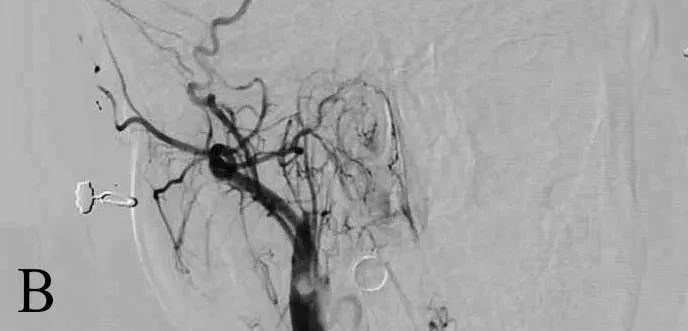

B:右侧ICA造影正位显示右侧ICA闭塞

F:去骨瓣减压术后,广泛脑肿胀伴出血